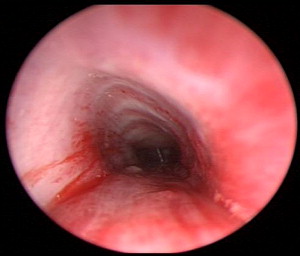

Microlaryngoscopy is performed with a rigid anterior commissure-type laryngoscope such as a Benjamin or Parsons placed in the vallecula ( Fig. 2 ) and used to expose the endolarynx and subglottic airway. This will reveal a subglottic hemangioma just below the vocal cords ( Fig. 3 ). Magnification from a Storz Hopkins telescope is used to visualize the subglottic airway and the scope can be passed down to the level of the carina. It is important to carefully look at the trachealis muscle in the back wall of the trachea for staining, fullness, and signs of vascular disease ( Fig. 4 ). Tracheal hemangioma may be subtle and its treatment is challenging.

Less common sites affecting the airway include postcricoid, tracheal, mediastinal, thoracic, and esophageal. They may stain the posterior trachealis muscle (see Fig. 4 ). Airway symptoms include biphasic stridor and recurrent croup. Diagnosis may be suggested by history and lack of another cause of subglottic stenosis, such as prolonged intubation. Plain neck films may suggest the diagnosis.